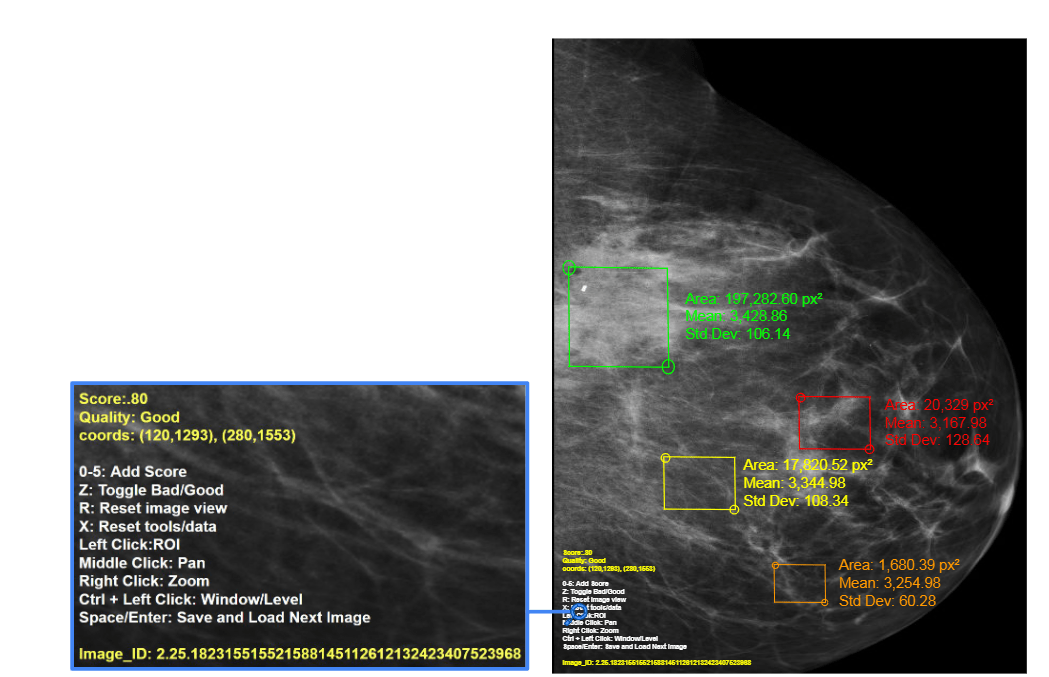

Web-Based Annotation Tool

white/0.00, red/0.20, orange/0.40, yellow/0.60, green/0.80, and blue/1.00